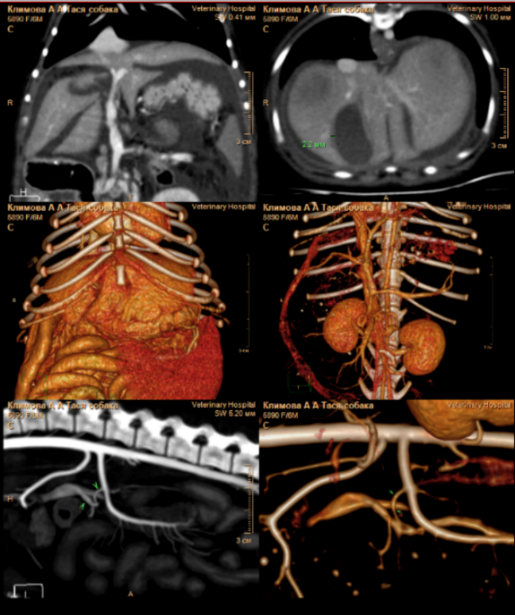

В этот период состояние пациента ухудшилось (фото 3), прогрессировал более выраженный асцит. Это привело к затруднению двигательной активности собаки, и владельцы приняли решение о повторном проведении ультразвукового исследования брюшной полости.

В ходе проведения УЗИ выявлена отрицательная динамика в отношении количества свободной жидкости в брюшной полости (до 6 см на просвет). Также обнаружены увеличение отека паренхимы поджелудочной железы, характеризующееся появлением признаков, известных как «тигровая поджелудочная железа», и нефролитиаз (фото 4). Данные изменения свидетельствуют о развитии тяжелой портальной гипертензии, что требует проведения незамедлительной диагностики для установления причин и разработки плана лечения.